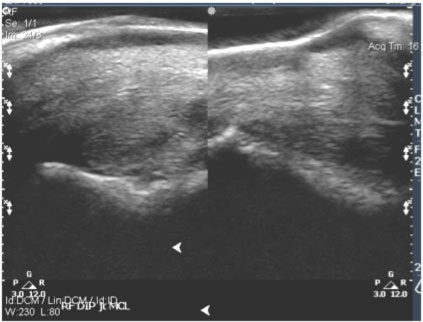

Example 1: 11-year-old quarter horse

History: Moderate tear of the medial collateral ligament of the right front coffin joint.

Left image: Sonogram of medial collateral ligament of right front coffin joint, showing enlarged cross-sectional area and a fresh-appearing core lesion.

Ultrasound Impressions: Image on the right was taken 3 months after image on the left and according to the veterinarian it shows reduced effusion and reduced synovitis in comparison with the previous examination. He stated that the lateral collateral ligament was normal and there has been a decrease in inflammation in the coffin joint and good granulation in the core lesion of the medial collateral ligament. Horse was treated twice daily on the Vitafloor.